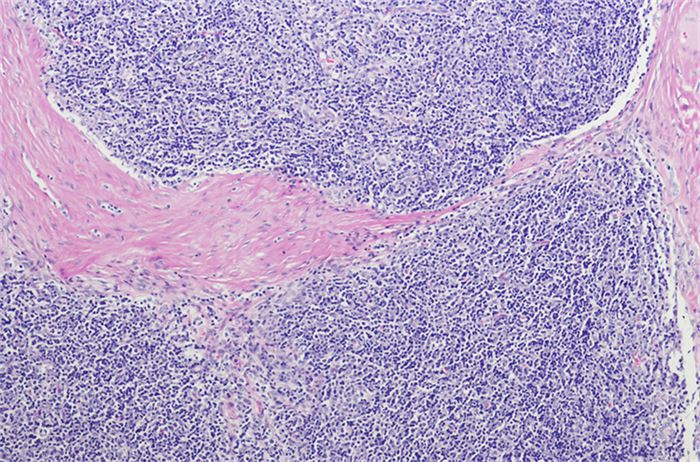

胸腺瘤的临床病理学研究:深入了解罕见肿瘤的病理特征

摘要:胸腺瘤是一种罕见的肿瘤,其病理学特征对于准确诊断和个体化治疗具有重要意义。本文综述了胸腺瘤的临床病理学研究进展,包括病理分类、组织学特征、免疫组化标记和分子病理学等方面的研究,以期为胸腺瘤的病理诊断和治疗提供新的视角和策略。引言胸腺瘤是一种发生在胸腺中的...